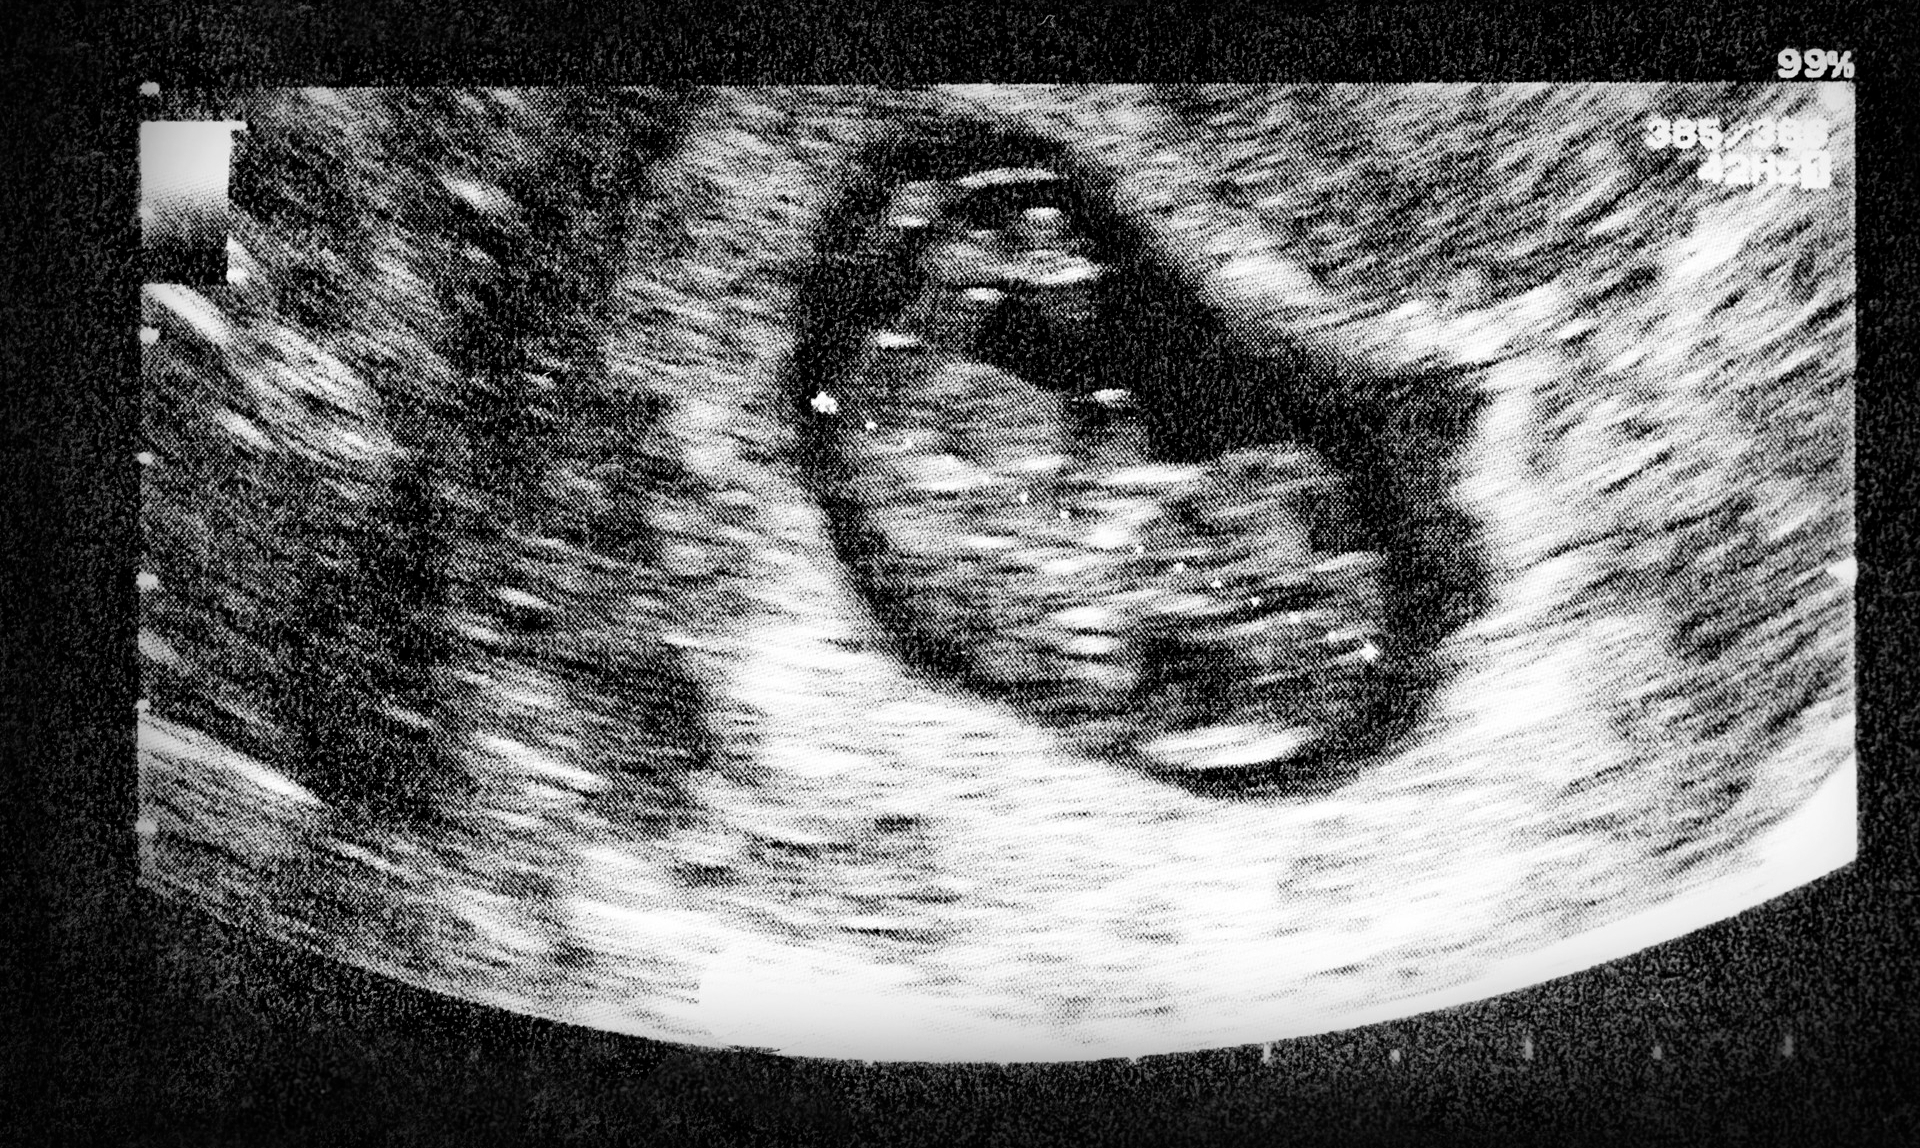

Placental health is essential for a safe pregnancy and healthy fetal development.

A placenta scan provides detailed assessment of placental position, structure, and function. Under the care of Dr Devi Subramanian, these scans offer reassurance and early detection of any placental problems that may affect your pregnancy.

The scan assesses

• Placenta location (anterior, posterior, fundal, low-lying)

• Distance from the cervix

• Placental maturity and appearance

• Blood flow using Doppler

• Evidence of accreta or attachment issues

Placenta praevia, for example, occurs when the placenta lies low in the uterus and may obstruct the cervix. Early detection allows careful planning for delivery, often through a planned caesarean, ensuring safety for both mother and baby.

Placenta scans are also essential for monitoring placental insufficiency, which may reduce the baby’s oxygen or nutrient supply. In such situations, further growth monitoring and Doppler studies are recommended.